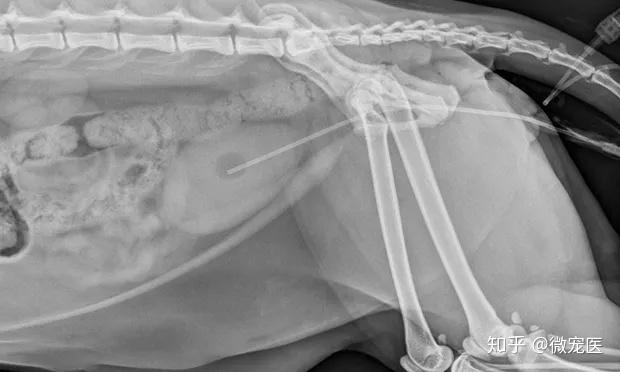

公猫膀胱结石!公猫尿闭!服用中药俩个月!x光前 - 抖音

图片尺寸1920x1080